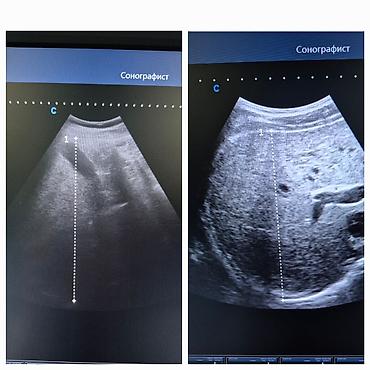

Услуга: УЗИ-диагностика опорно-двигательного аппарата, внутренних органов и органов малого таза

Профессиональное ультразвуковое исследование:

- Брюшная полость и забрюшинное пространство: печень, желчный пузырь, поджелудочная железа, селезёнка, почки, мочевой пузырь.

- Визуализация мелких анатомических структур, измерения с документированием.

- Работа линейными и конвексными датчиками для высокой детализации поверхностных и глубоко расположенных тканей.

- Фото- и видеопротокол исследования с разметкой ключевых зон.